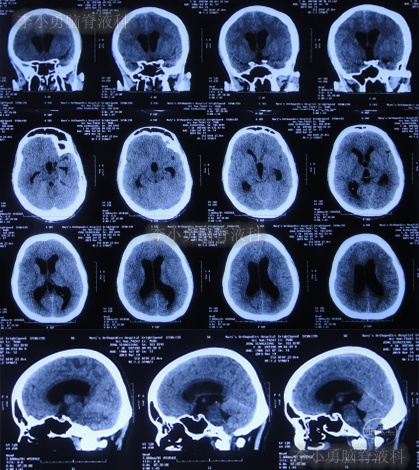

入院当天头颅CT示小脑扁桃体下疝减压术后,枕下可见低密度影。脑室系统稍扩张(图-12);颈椎核磁脊髓可见空洞形成(片子丢失)。

图-12:2019年3月19日入院时头颅CT

图-13:入院当天术后头颅CT

入院治疗3天即2019年3月22日,头痛减轻(图-14),查头颅CT示较入院时缩小(图-15)。

图-15:2019年3月22日头颅CT